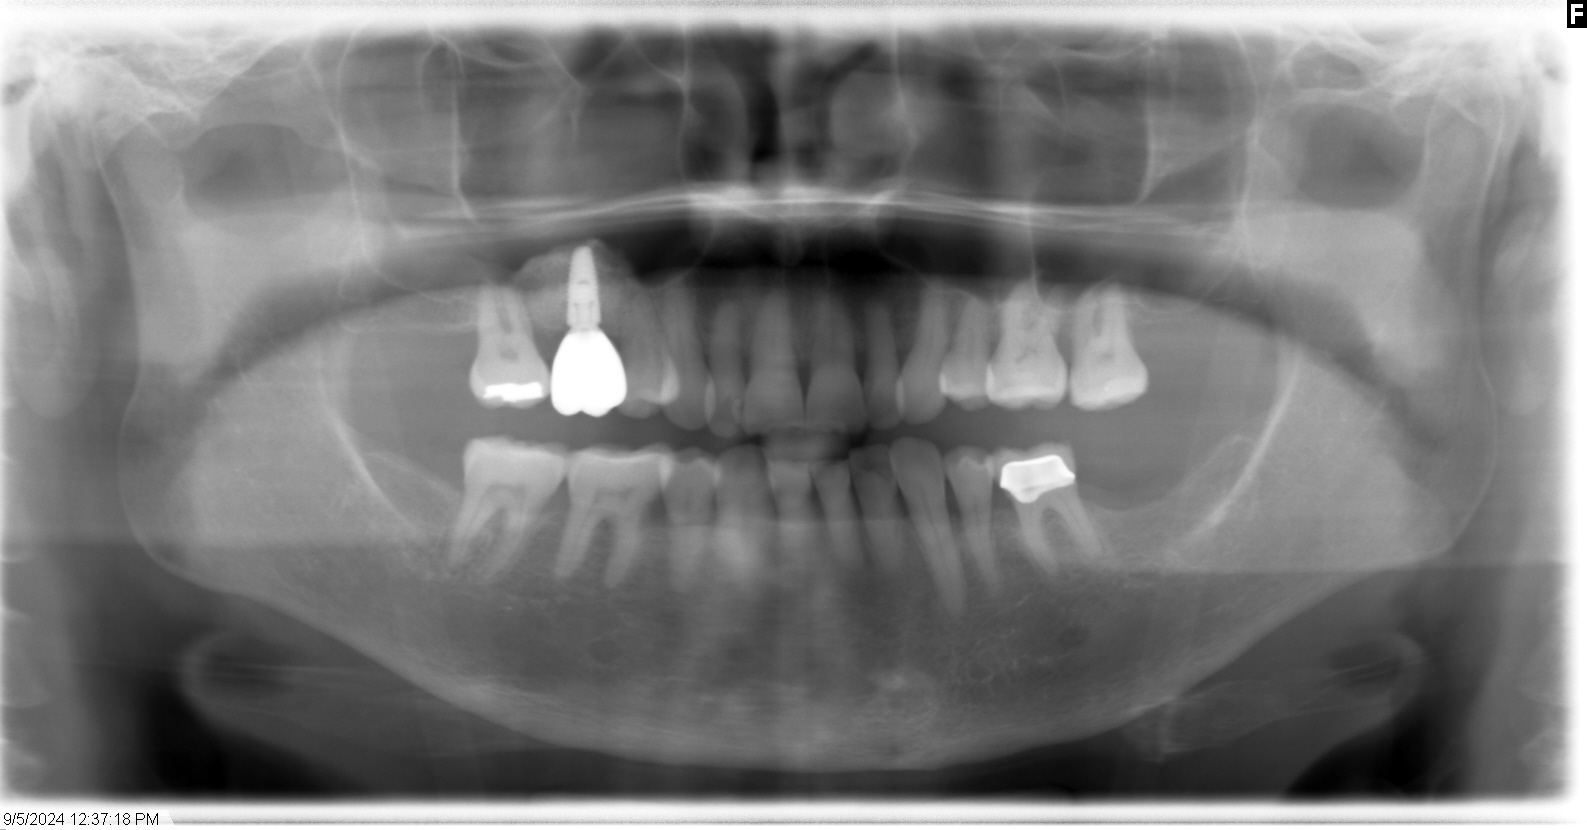

サイナスリフト後、治癒期間をおいて十分な骨の形成を確認し、インプラントを埋入しました。

その後、インプラントと骨の結合を確認し、最終補綴物を装着して治療を終了しました。

初診時

術後